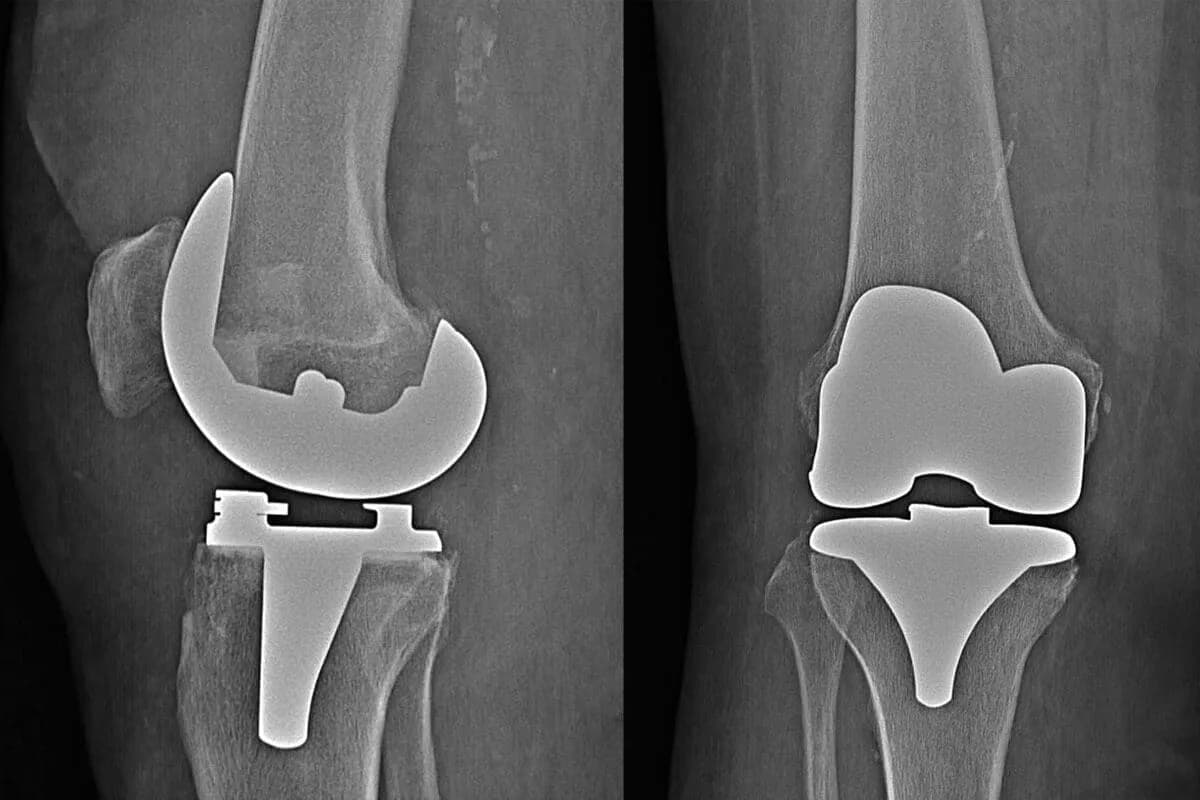

RTG stawów: Dlaczego obrazowanie jest istotne przed zabiegiem

RTG stawów to kluczowe badanie, które pozwala na dokładną ocenę stanu stawów przed operacją endoprotezy. Dzięki zdjęciom rentgenowskim lekarze mogą zobaczyć wszystkie zmiany patologiczne, takie jak uszkodzenia kości, zmiany zwyrodnieniowe czy deformacje, które mogą wpływać na przebieg operacji. Obrazowanie stawów jest niezbędne do zaplanowania odpowiedniego podejścia chirurgicznego oraz wyboru właściwego rodzaju endoprotezy. Bez tego badania, ryzyko powikłań podczas operacji może znacznie wzrosnąć.Przygotowanie do badań przed operacją endoprotezy: Co musisz wiedzieć?